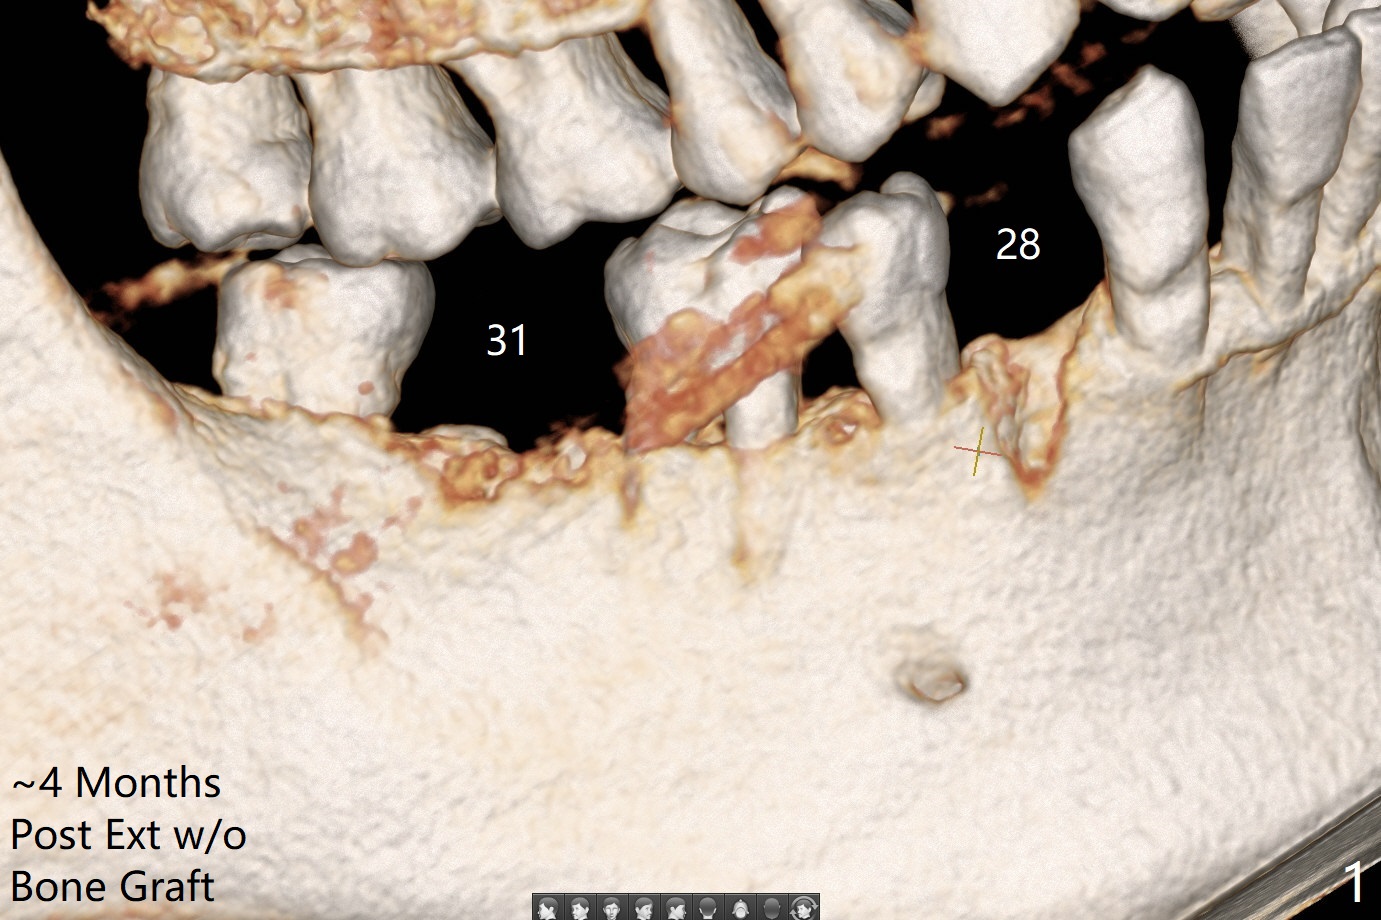

Bone Density Post Extraction with or without Bone Graft

Critical Area